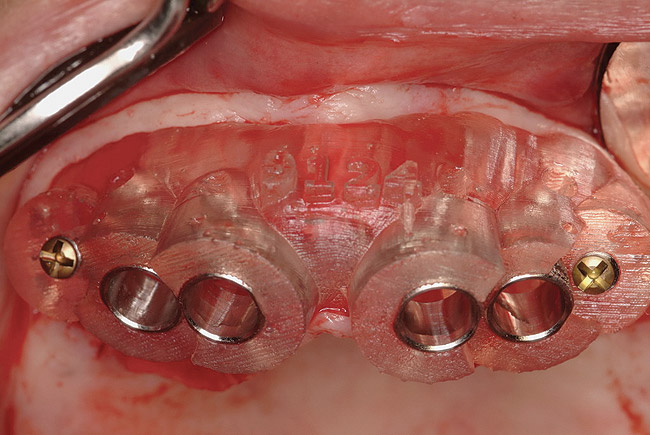

Figure 11  Stent stabilized with fixation screws.

Figure 11

These patients were tested for two different treatment options; either a bar-supported overdenture requiring four implants in the first premolar area or anterior to the bicuspids, or a "simple fixed prosthesis" anchored by six implants placed bilaterally from first-molar-to-first-molar regions. When a flapless, guided surgery was contemplated, the investigators determined that based on the available maxillary bone, 70% of patients (28 implants) could undergo this treatment modality. Of the 40 patients, 15% could not have any implants placed due to inadequate bone height and width. For "simple fixed prostheses," only 30% (72 implants) of patients presented with adequate bone dimensions permitting a flapless guided placement of six maxillary implants placed symmetrically around their arch in a flapless manner. For the fixed treatment, 18% of patients could not have any implants placed due in insufficient bone dimensions. The authors concluded that advertisement of computer-guided, flapless solutions are "euphoric," and tend to overlook patients' individual oral and anatomic conditions. They felt that guided surgery does provide better control of implant placement leading to higher predictability of treatment outcomes. In a study where the accuracy of virtually placed implants and actual positions in a cadaver model were compared, Petterson et al7 found significant differences related to deviations in hex, apex, and depth of the two placements. Without the preparedness to temper treatment expectations or plan on delivery of the pre-fabricated "final" prosthesis immediately after surgery, these types of studies should lead clinicians to proceed with caution in these procedures. The efficacy of an open approach, one requiring a mucoperiosteal flap, may be improved upon with a guided approach in cases where severe ridge-resorption is treated, and may be more predictably handled using this technology. A bone-supported template, affixed to the alveolar ridge with fixation screws, can be fabricated with numerous software package and stereolithography (Figure 8 and Figure 9). A full-thickness flap is elevated, exposing the resorbed alveolar ridge (Figure 10). Using osseous fixation screws, the template is stabilized to the ridge, preventing any movement during osteotomy preparation (Figure 11). Using a sleeve-in-sleeve, manufacturer-specific surgical armamentarium, implants can be placed in the optimal positions, where the maximum amount of initial bone to implant contact is achieved. The anticipated bone augmentation procedures can then be performed, which is not possible with a closed procedure (Figure 12). The flaps are subsequently closed, allowing for the patient to wear any transitional, soft-relined denture. The surgical guide can also serve an important function at the time of implant uncovering. The location of the implants beneath the healed mucosa can be determined by seating the guide and sounding with a 30-gauge anesthetic needle. Using a tissue punch, the implants can be uncovered without flap elevation; the cover screws can be removed and the appropriately sized healing abutments can be placed (Figure 13). From this point forward, traditional prosthetic steps are followed to fabricate an implant-supported/retained overdenture.